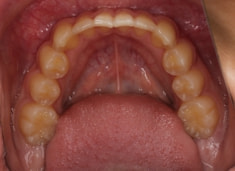

治療前

治療開始時